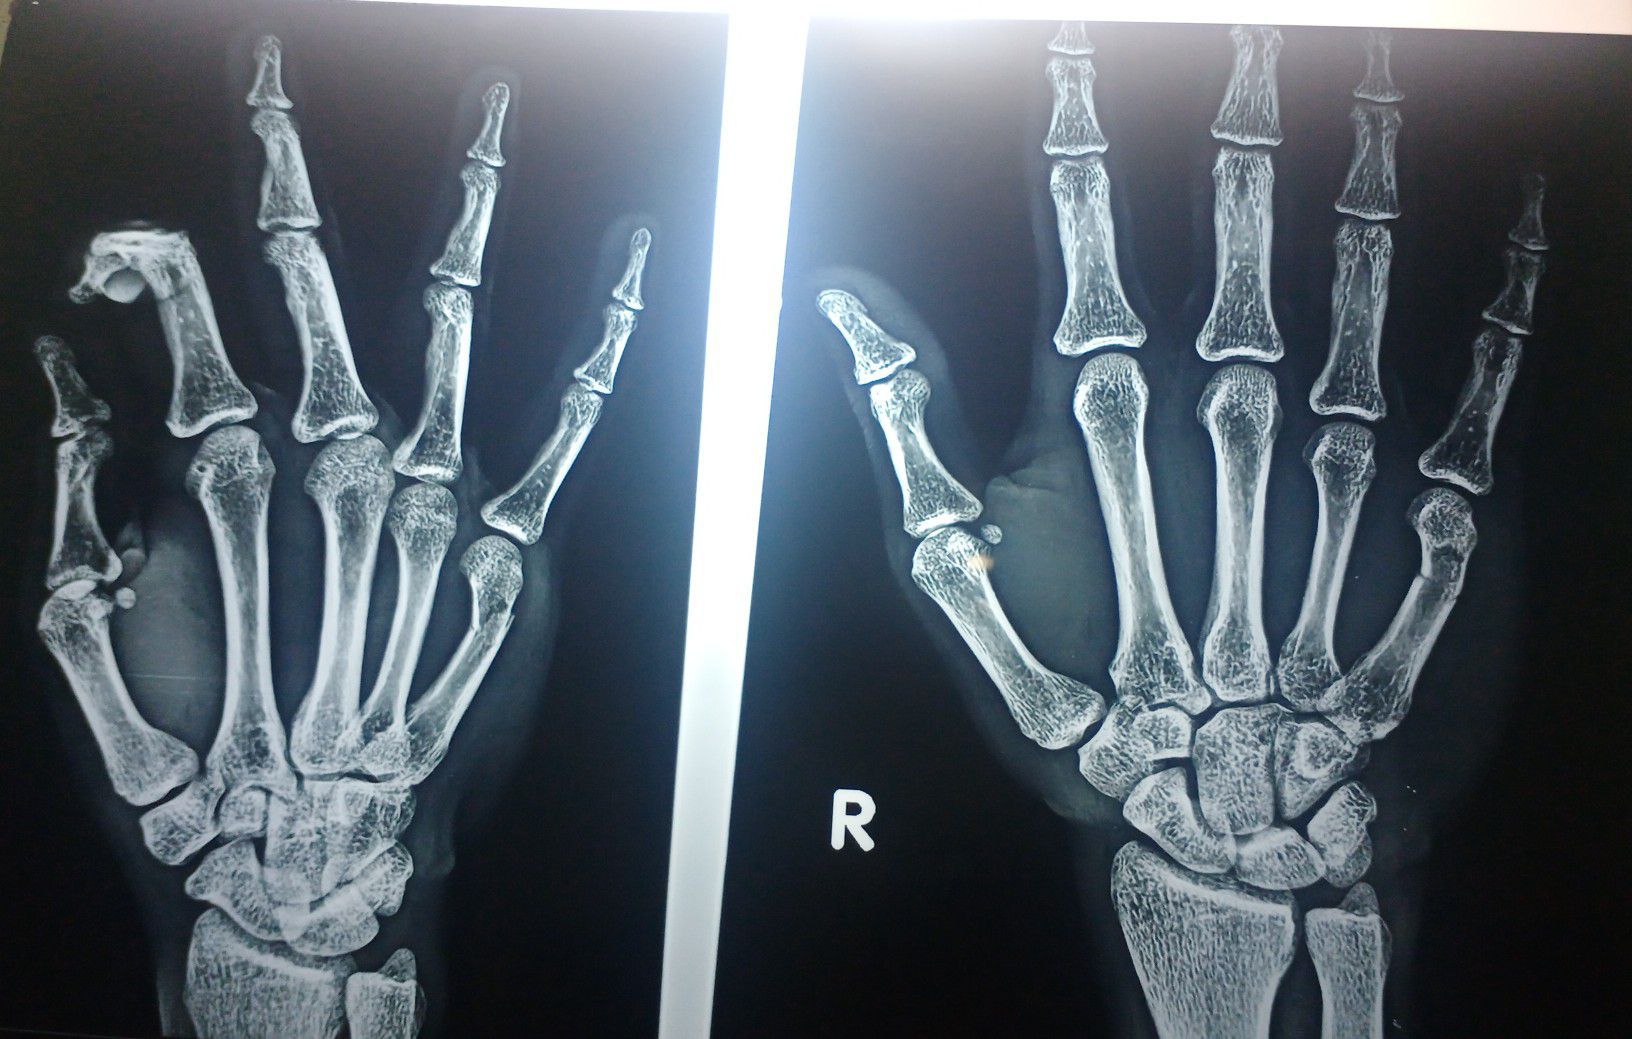

Metacarpal fracture

Fracture of 5th metacarpal bone managed by applying ulnar gutter cast .